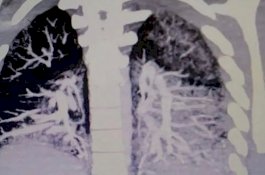

Awalnya Dikira Bronkitis, Remaja Pecandu Vaping Ini 'Simpan' Minyak di Paru-paru